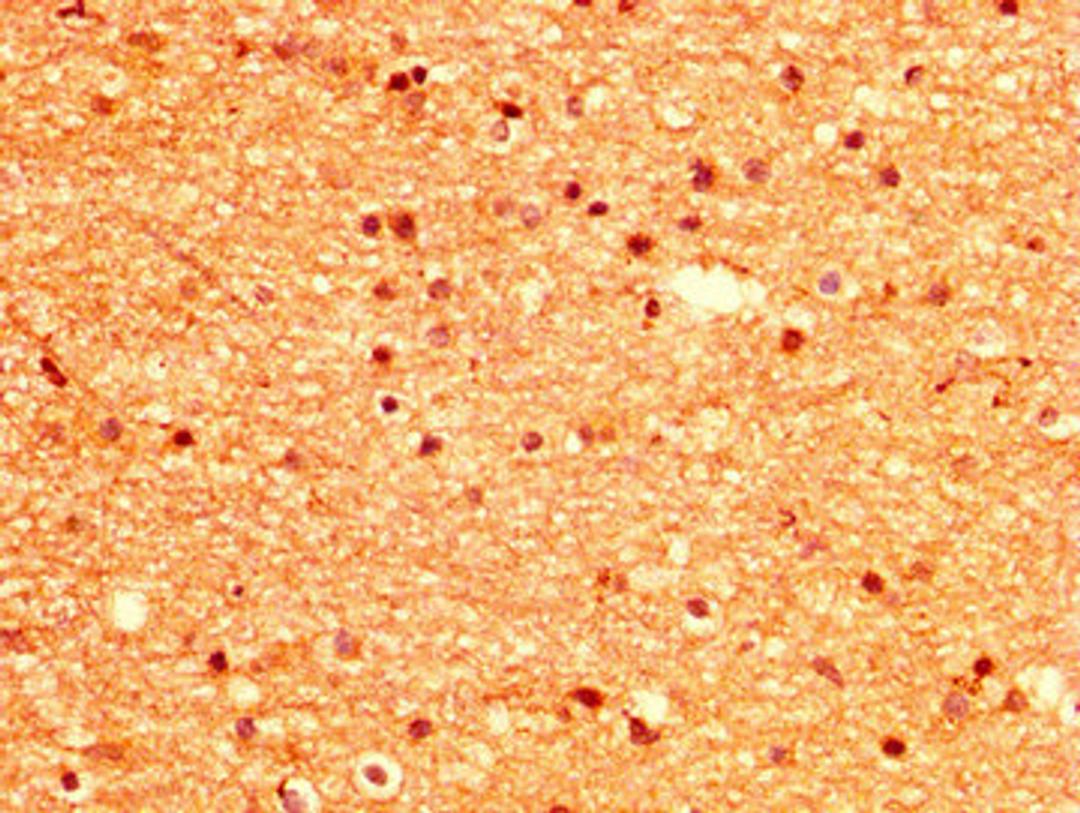

IHC image of CSB-PA015033LA01HU diluted at 1:500 and staining in paraffin-embedded human brain tissue performed on a Leica BondTM system. After dewaxing and hydration, antigen retrieval was mediated by high pressure in a citrate buffer (pH 6.0). Section was blocked with 10% normal goat serum 30min at RT. Then primary antibody (1% BSA) was incubated at 4°C overnight. The primary is detected by a biotinylated secondary antibody and visualized using an HRP conjugated SP system.